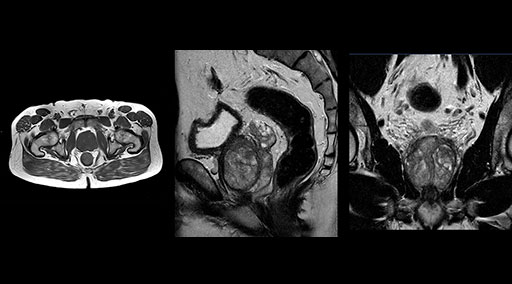

“Without using an endorectal coil we do our prostate MR at 0.5 mm resolution, following the European society of urology protocol [1]. For certain joints we use a virtual arthroscopy protocol with 1 mm pixel size and 2 mm slice thickness. Ingenia really excels in our neurography, brachial plexus and prostate scans. Our neurologists insist on using our 3.0T for those,” Dr. Kaakaji adds.

Patrick Duffy BS, RT (R) MR is Lead Technologist at DMG. “We are getting phenomenal image quality on all types of exams,” he says. “Our MSK is stellar, and so is our abdominal work. Ingenia excels at feet, hands and fingers. We do enterographies with great results. With the combination of the 3.0T magnet and the digital coils, we are able to scan prostates without an endorectal coil while still obtaining high quality results. This is a comforting experience for our male patients. We scan many obese patients, and the Ingenia does a tremendous job because of MultiTransmit, which reduces dielectric shading for more confident diagnosis. Our technologists really enjoy scanning on the Ingenia. We also have ordering physicians who specifically want their patients scanned on the Ingenia because of the results of our imaging.

“Our DMG Lisle location includes a cancer center, so soft tissue neck scans, brachial plexus scans, and prostate scans are common. For these exams, mDIXON TSE provides excellent images with and without fat suppression all while helping us reduce repeats and work more efficiently,” Mr. Duffy says.